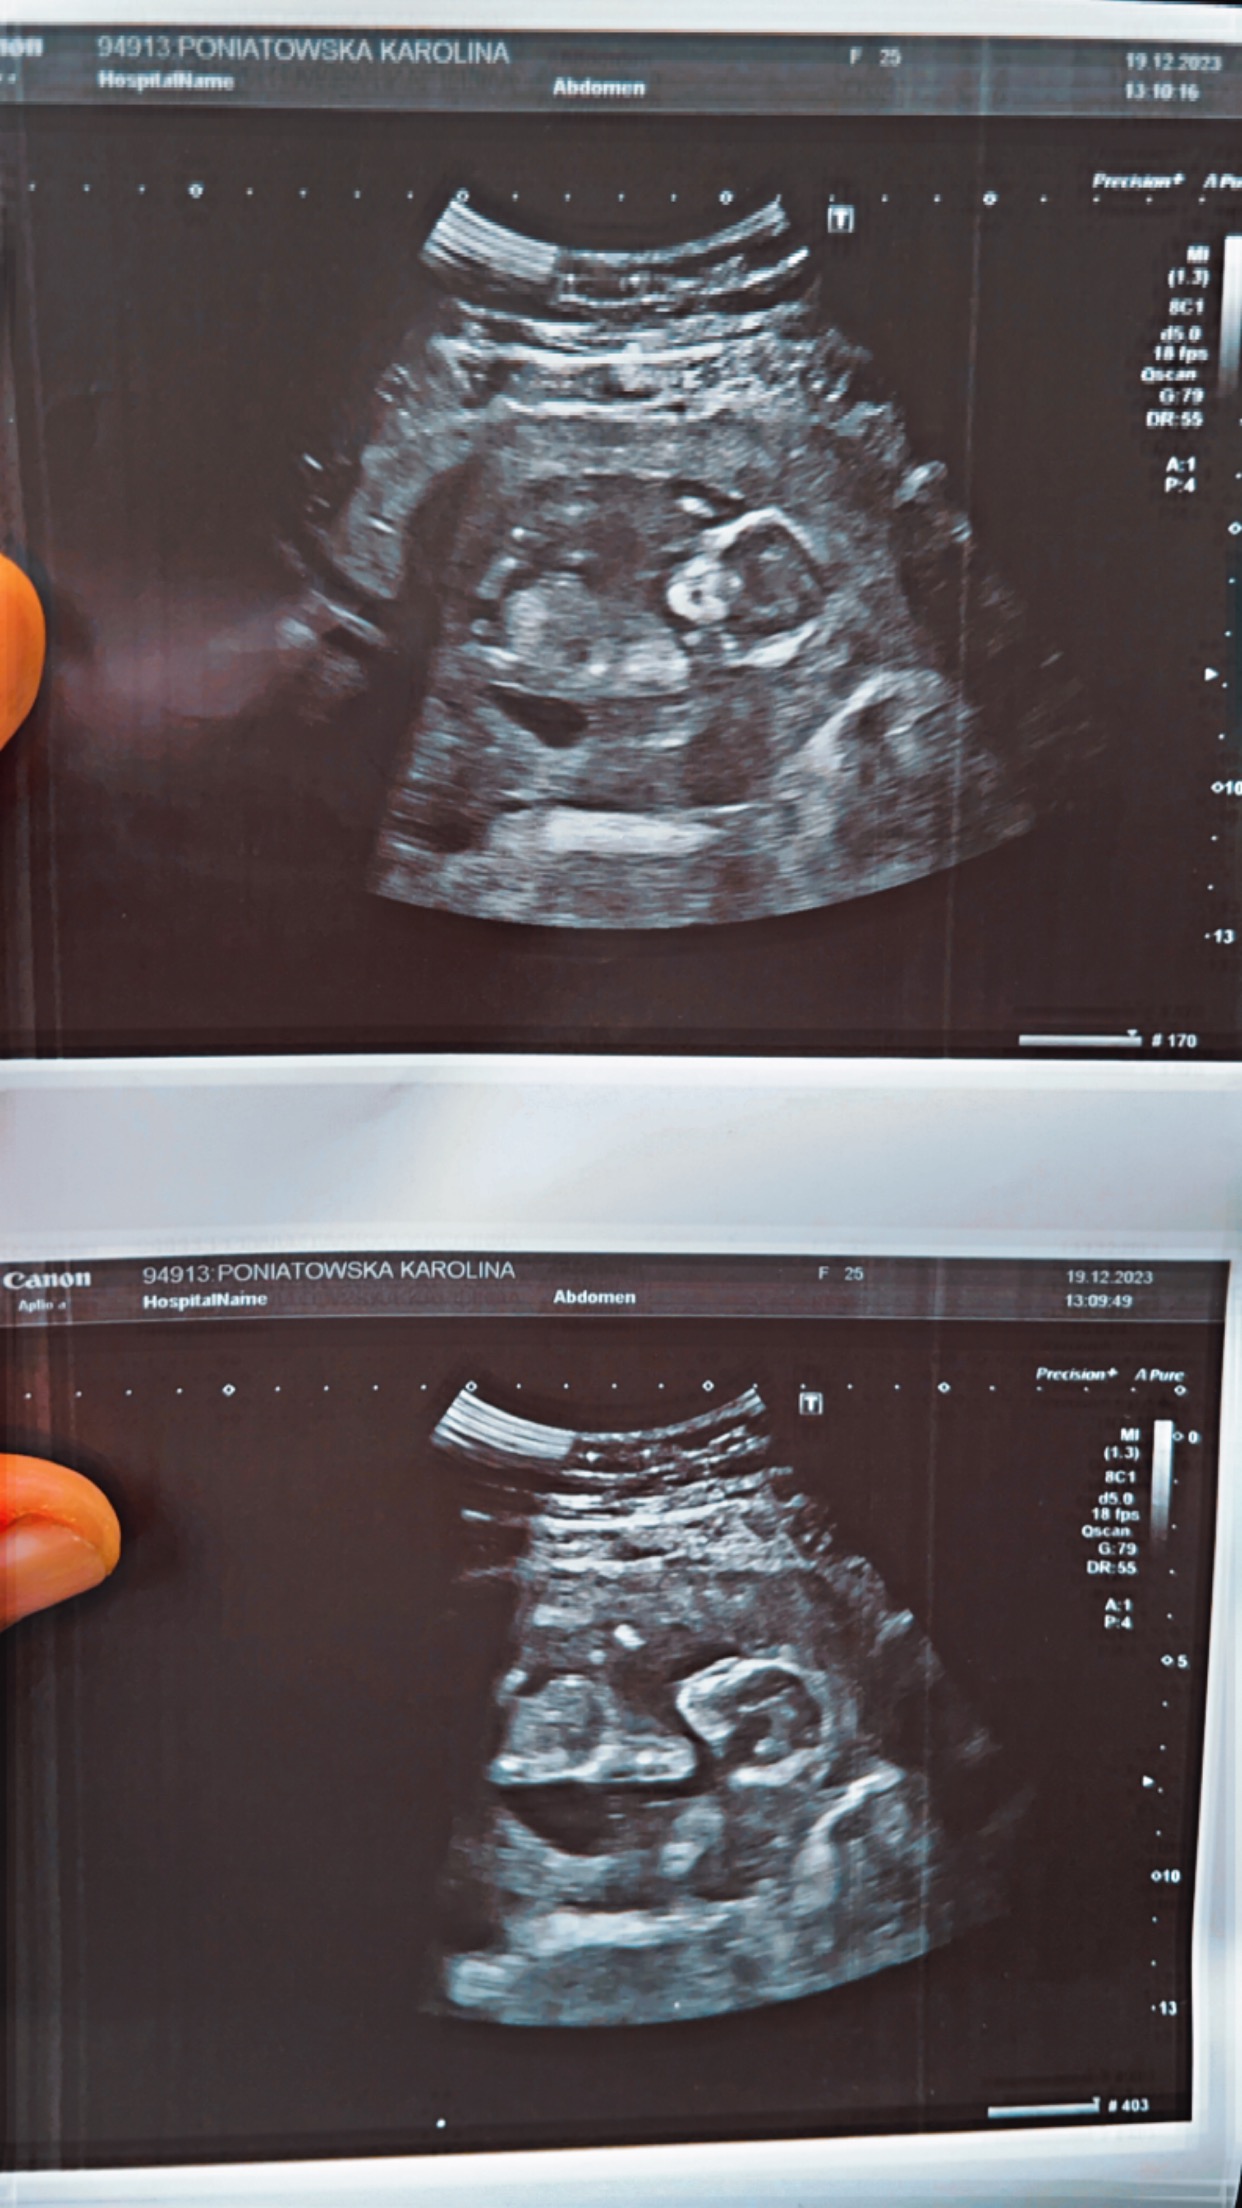

A co powiedział lekarz?Witam. Czy coś widać na tym zdjęciu czy chłopak czy dziewczyna, ciekawość mnie zjada. 16tc

Wydaje mi się, że na pierwszym zdjęciu widzę chłopca, ale to oczywiście na podstawie wyłącznie przeglądanych przeze mnie zdjęć nubów i potem narządów zewnętrznych na usg na FB i w GoogleWitam. Czy coś widać na tym zdjęciu czy chłopak czy dziewczyna, ciekawość mnie zjada. 16tc

Obecnie już 18 tydzień i powiedział że prawdopodobnie chłopiec będzieWydaje mi się, że na pierwszym zdjęciu widzę chłopca, ale to oczywiście na podstawie wyłącznie przeglądanych przeze mnie zdjęć nubów i potem narządów zewnętrznych na usg na FB i w GoogleDaj znać co powiedział lekarz